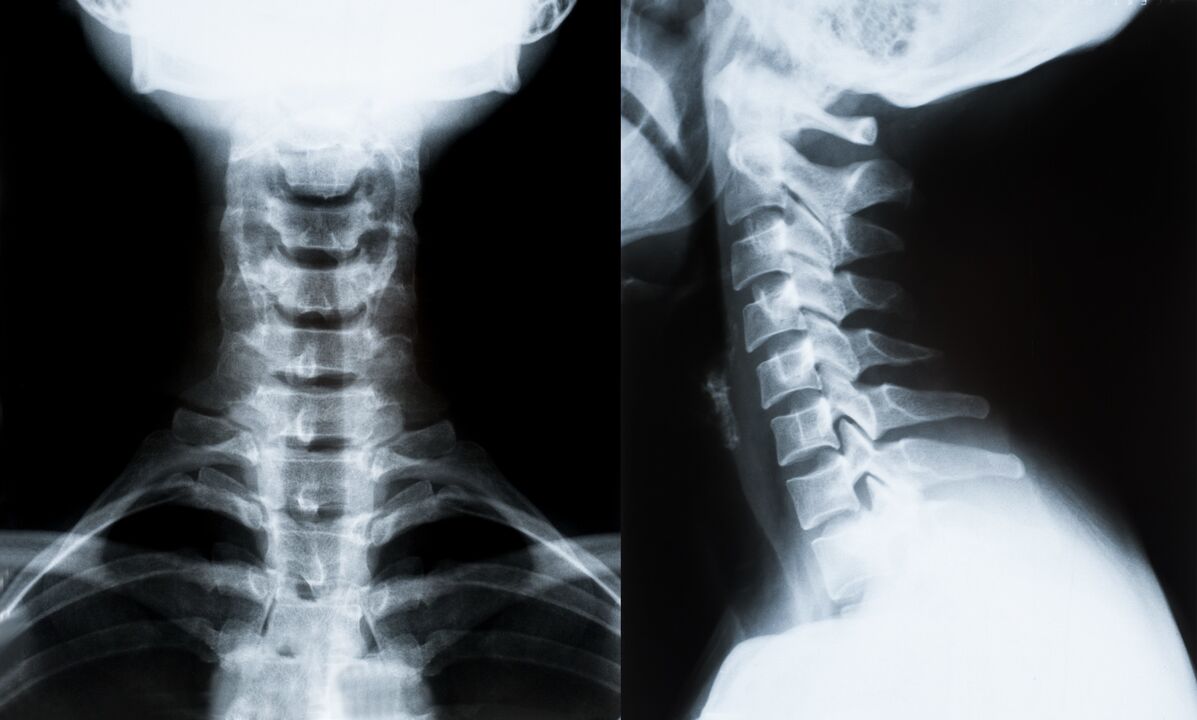

Les principales méthodes de diagnostic et de détermination ultérieure du traitement de l'ostéochondrose de la colonne cervicale :

- Rayons X. La méthode de diagnostic la moins efficace, mais traditionnelle.

- L'imagerie par résonance magnétique est la méthode de diagnostic la plus efficace. Avec ce type d’examen du patient, toutes les structures nécessaires sont visibles.

- S'il est nécessaire de mesurer les changements, une tomodensitométrie est utilisée. Détermine la présence de hernies et d'autres choses.

- La dernière méthode est l’échographie duplex. Cette méthode de recherche détermine la vitesse du flux sanguin dans les artères.